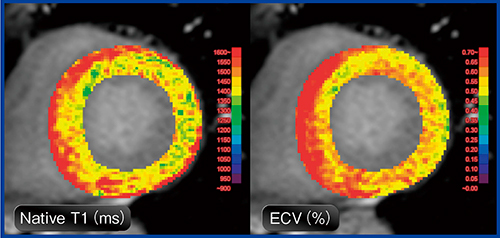

図1 MR心筋T1マッピングによる心筋評価:心アミロイドーシス

心筋壁のNative T1〔平均1480ms(施設基準値1230ms)〕とECV〔平均61%(基準値23〜28%)〕が,びまん性かつ顕著な異常高値を示している。ECVが40%以上を呈する場合は心アミロイドーシスを強く疑う必要がある3)。